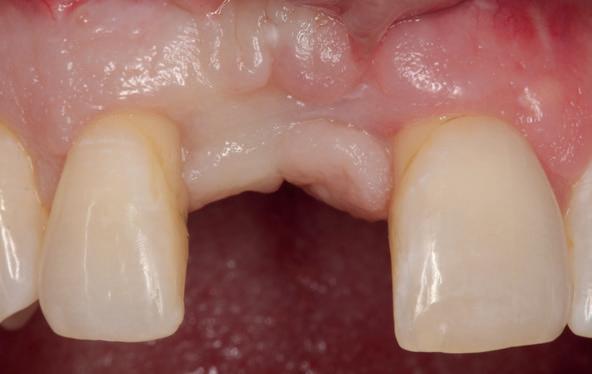

Implantologische behandelingen in het esthetische front vragen meer dan technische vaardigheid alleen. Ze vragen om overzicht, timing, vertrouwen en een team dat als vanzelf samenwerkt onder druk. Juist bij complexe casussen, waarin angst, infectie en hoge esthetische verwachtingen samenkomen, wordt zichtbaar hoe bepalend de rol van de tandartsassistent is.

Deze casus beschrijft een uitgebreide immediate implantaatbehandeling bij een patiënt die door meerdere collega’s werd geweigerd. Niet omdat de mogelijkheden ontbraken, maar omdat de complexiteit vroeg om een perfect afgestemde samenwerking. Het verhaal laat zien hoe de assistent in zo’n traject veel meer is dan een uitvoerende kracht of “mal”, maar een dynamische surgical guide die het proces mede stuurt, bewaakt en mogelijk maakt.De patiënt: wanneer alles samenkomt

De kern van haar vraag was eenvoudig en tegelijkertijd uitdagend: Is het mogelijk om mijn huidige brug te dupliceren en een nieuwe brug te vervaardigen met minder complicaties?